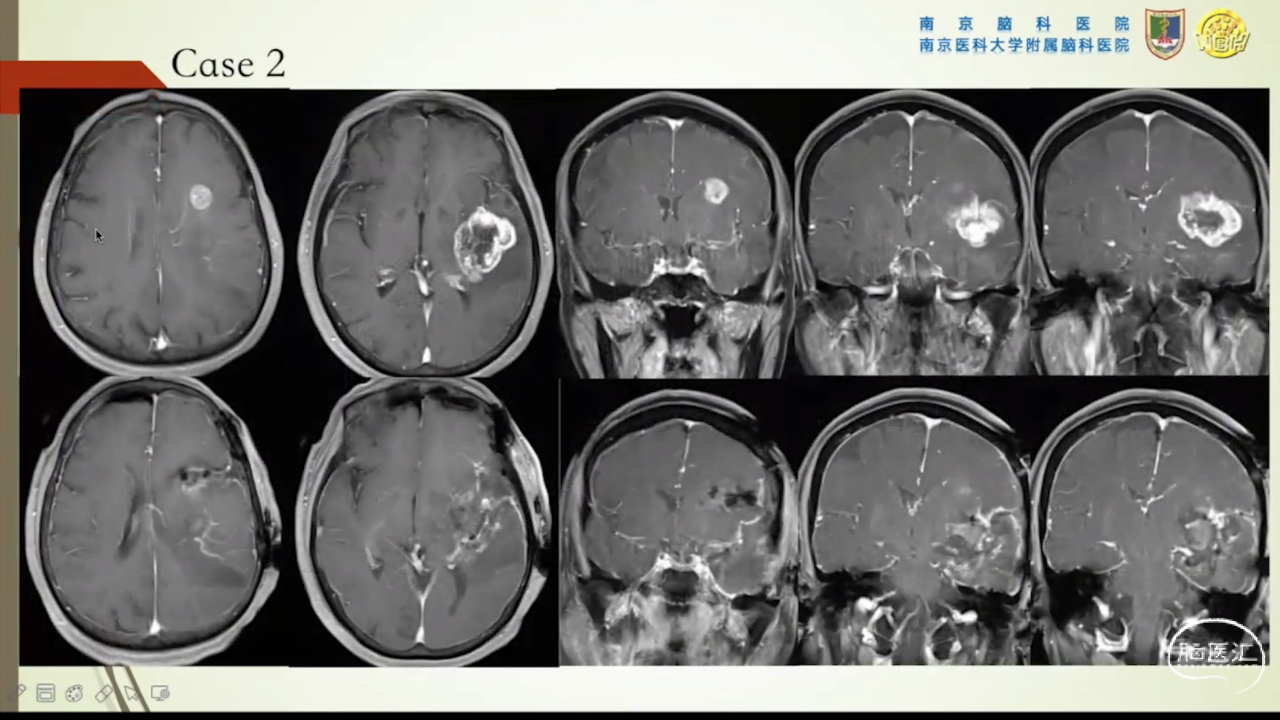

胶质瘤是发病率最高的颅内肿瘤(约占44.69%),岛叶是神经胶质瘤的好发部位,大约有25%的低级别胶质瘤及10%的高级别胶质瘤发生在岛叶,大多数岛叶胶质瘤为低级别胶质瘤。岛叶在调节内脏感觉运动、控制心血管交感活性、传入躯体感觉中均起重要作用。它也参与了痛觉的传递、运动规划、自主性吞咽、味觉、听觉、前庭功能、情绪、认知能力和语言能力。因为岛叶解剖结构复杂,并覆盖有高级语言皮层、白质束及重要的血管结构,故岛叶部位的手术难度极大。

讲题岛叶胶质瘤的显微手术治疗